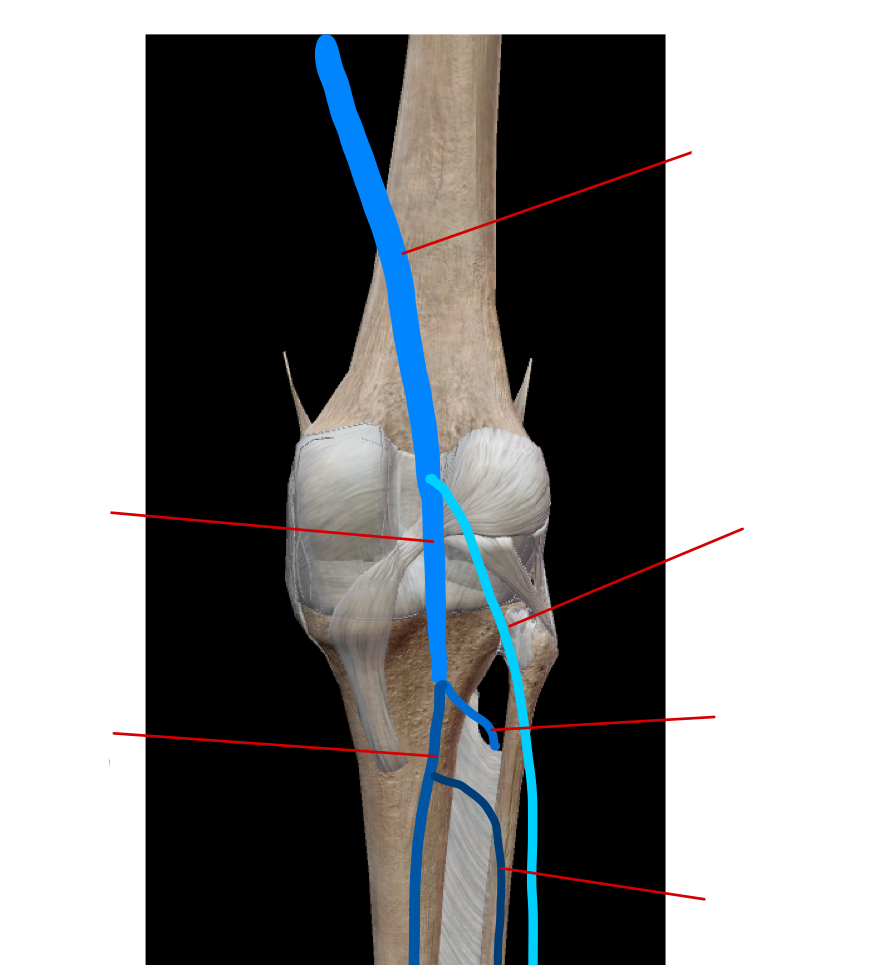

label the veins in the hip region

label the vein in the lower limb